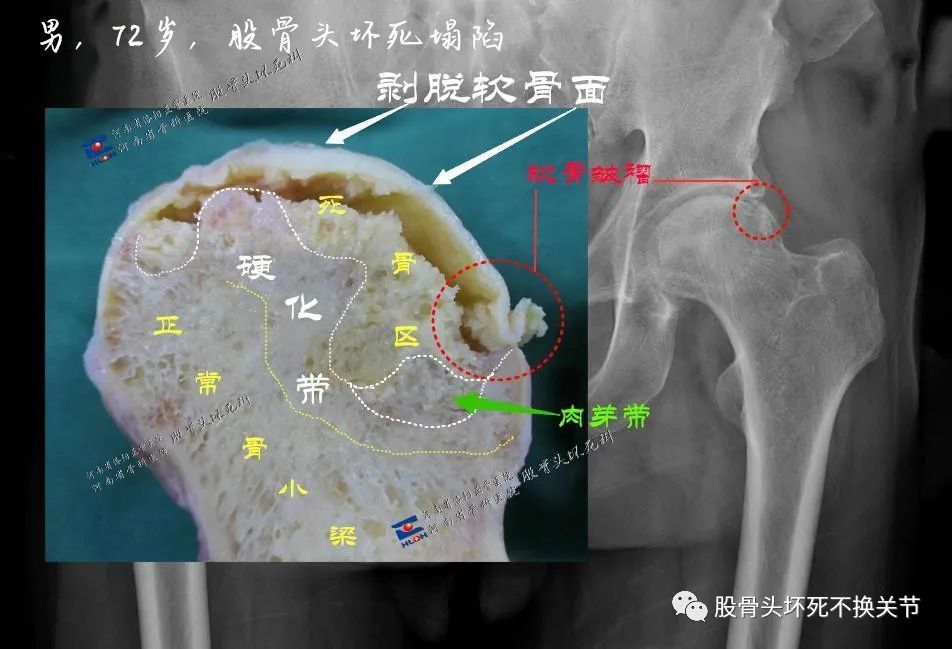

如上所示,左侧股骨头箭头所指区域,为骨密度硬化带,其内则为坏死灶减低区。为便于理解,可参照下方股骨头剖面图:

本案病人22岁,显然不能按照上图72岁病人那样进行关节置换,给他一次保头的机会还是很有必要的。当然制定治疗计划,需要参照CT检查,进一步明确股骨头内的骨质质量。